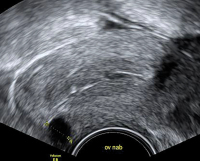

Tipps und Tricks im Gyn-Ultraschall: Ovula Nabothii – Die Eier des Martin Naboth. Wissenswertes zu einem Nebenbefund

Journal für Gynäkologische Endokrinologie 2016; 10 (1) (Ausgabe für Österreich): 12-14 Journal für Gynäkologische Endokrinologie 2016; 10 (1) (Ausgabe für Schweiz): 12-14 Volltext (PDF) Abbildungen